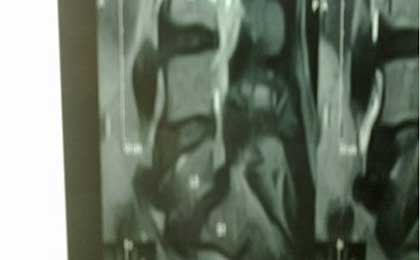

PRE OP MRI SPINE INJURY

PRE OP L5-S1 MRI